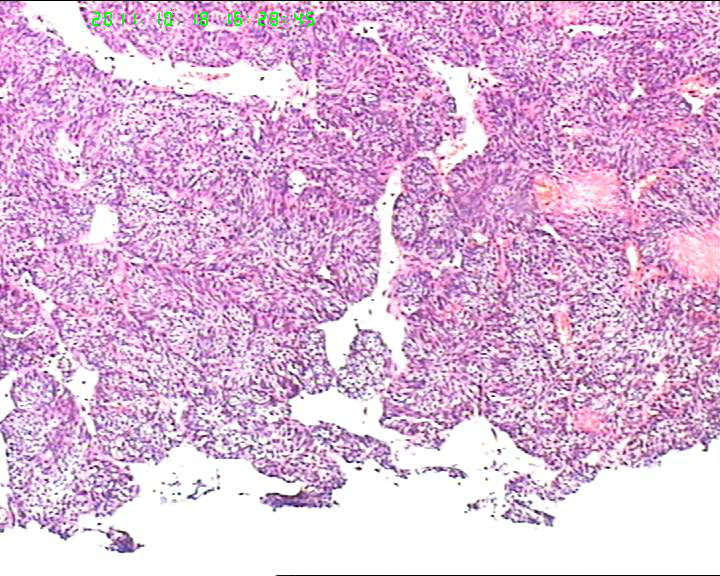

70岁女性体检发现膀胱肿物,是癌吗?

膀胱后壁一2*1cm大小肿物